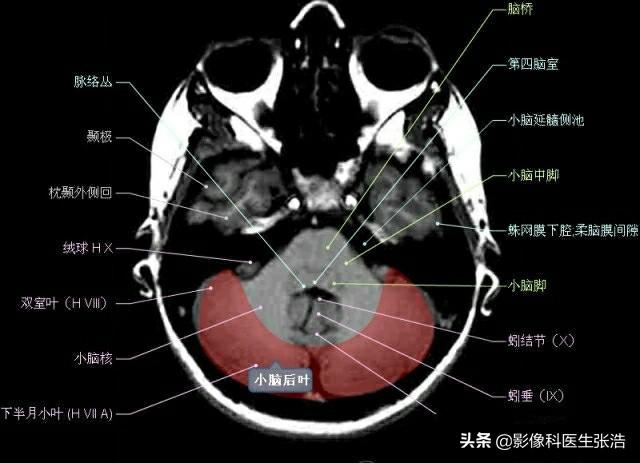

核磁共振(MRI)是一種利用磁場和射頻脈沖來生成身體內(nèi)部結(jié)構(gòu)的詳細(xì)圖像的非侵入性檢查技術(shù),頭部核磁共振主要用于檢查腦部疾病、神經(jīng)系統(tǒng)問題以及血管狀況等,這項(xiàng)檢查對(duì)于疾病的早期發(fā)現(xiàn)和治療具有非常重要的意義。